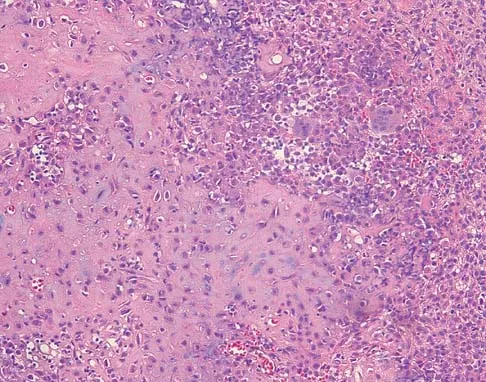

A 16-year-old girl has had pain in the left groin for the past 4 months. She notes that the pain is worse at night; however, she denies any history of trauma and has no constitutional symptoms. There is no history of steroid or alcohol use. Examination reveals pain in the left groin with rotation of the hip. There is no associated soft-tissue mass. A radiograph and MRI scan are shown in Figures 32a and 32b, and biopsy specimens are shown in Figures 32c and 32d. What is the most likely diagnosis?

Explanation

Based on the epiphyseal location and sharp, well-defined borders, the radiograph suggests chondroblastoma. Histologically, multinucleated giant cells are scattered among mononuclear cells. The nuclei are homogenous and contain a characteristic longitudinal groove. Although not seen here, "chicken-wire calcification" with a bland giant cell-rich matrix is also typical for chondroblastoma. Clear cell chondrosarcoma occurs in epiphyseal locations but has a more aggressive histologic pattern and occurs in an older age group. Giant cell tumors occur in the epiphysis but have a more uniform giant cell population histologically. Aneurysmal bone cyst often results in bone remodeling and has a different pathologic appearance. Osteonecrosis has a typical histologic pattern of empty lacunae and necrotic bone. Springfield DS, Capanna R, Gherlinzoni F, et al: Chondroblastoma: A review of seventy cases. J Bone Joint Surg Am 1985;67:748-755. Simon M, Springfield D, et al: Chrondroblastoma: Surgery for Bone and Soft Tissue Tumors. Philadelphia, PA, Lippincott Raven, 1998, p 190.